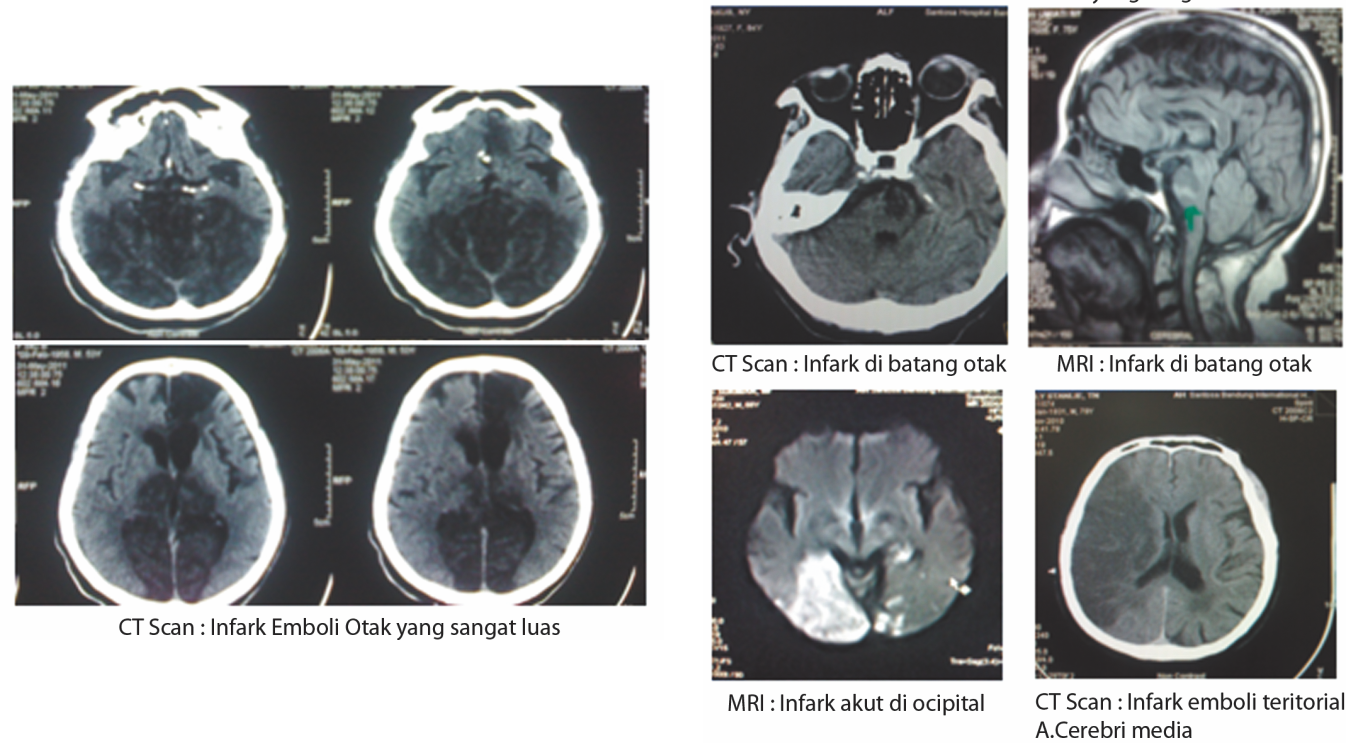

Infark (sumbatan) dan hemorrhage (perdarahan). Pada Stroke Infark terjadi sumbatan di pembuluh darah otak menyebabkan kematian jaringan otak. Merupakan jenis stroke terbanyak (85%), terdiri dari:

- Pemeriksaan CT Scan atau MRI Kepala